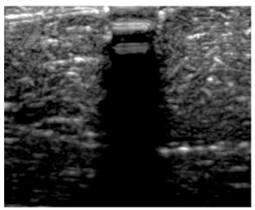

3.3. B-Mode Images

3.5. Echogenicity

4.1. Ultrasonography and Aerogel Dimensional Analyis

| Aerogel Type | US Image | Normalized Intensity Map | 3D Intensity Map | |

|---|---|---|---|---|

| 1 | Muscle |  |  |  |

| 2 | X-silica |  |  |  |

| 3 | X-silica-La2O2S:Eu |  |  |  |

| 4 | SMPU-Mix-14 |  |  |  |

| 5 | SMPU-Mix-18 |  |  |  |

| 6 | BRF-CA |  |  |  |

| 7 | ARF-CA |  |  |  |

| 8 | X-Ca-Alg-2 |  |  |  |

| 9 | X-Ca-Alg-1 |  |  |  |